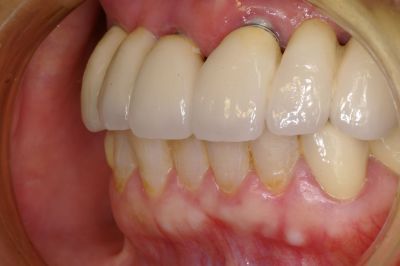

| A手術当日に仮歯のブリッジが入るオールオン6 (ノーベルバイオケア使用症例) |

| この症例の場合は、顎の骨の幅は、あまり広くはなかったですが 上顎洞までの距離があって13mmの長さのインプラントを選択することができたので 6本のインプラント(条件が整えばノーベルバイケアインプラント推奨)で行いました。 |

先の症例@の方と同じく、笑気麻酔などを使用しました。 総入れ歯と、このようになるのとでは咬めることはもちろん、気分が違ってきて若返られています。 |